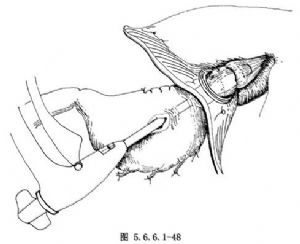

(9)收紧食管近侧断端的荷包缝线并打结,将食管残端固定在吻合器的中心杆上。转动吻合器主体机尾端的螺丝旋钮,逐渐调整抵订座和装订头之间的距离,使食管残端与要被吻合的胃壁紧密接触,但要防止过度挤压(图5.6.6.1-48)。